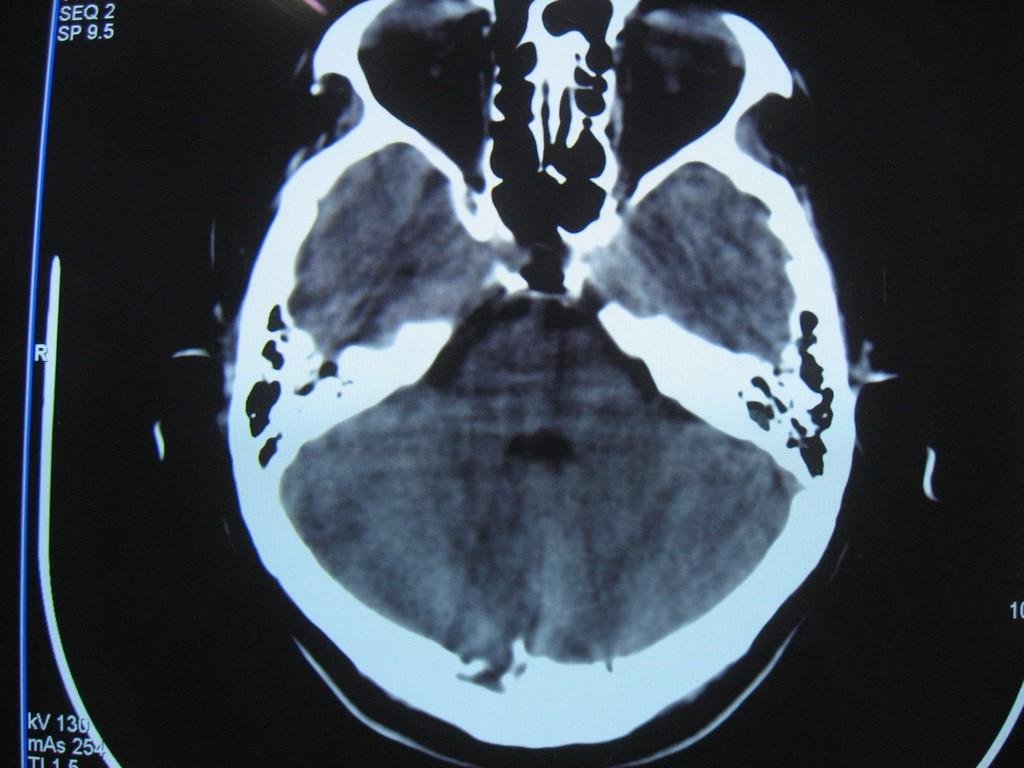

标题: CT22032B:枕骨破坏(从新调整窗宽窗位) [打印本页]

标题: CT22032B:枕骨破坏(从新调整窗宽窗位)

女性病人,53岁,偶尔感枕部针刺样疼痛,ct扫描如下。

蛛网膜颗粒压迹。鉴别:骨巨,嗜酸性肉芽肿,骨髓瘤。

蛛网膜颗粒压迹。

骨巨,嗜酸性肉芽肿,骨髓瘤,动脉瘤样骨囊肿可能

支持蛛网膜颗粒压迹。

支持蛛网膜颗粒压迹,鉴别:骨巨,嗜酸性肉芽肿,骨髓瘤、转移瘤

支持蛛网膜颗粒压迹,嗜酸性肉芽肿发生于30岁以下,基本排除,骨髓瘤、转移瘤多伴有软组织肿块,范围较广。

枕骨蛛网膜颗粒压迹。